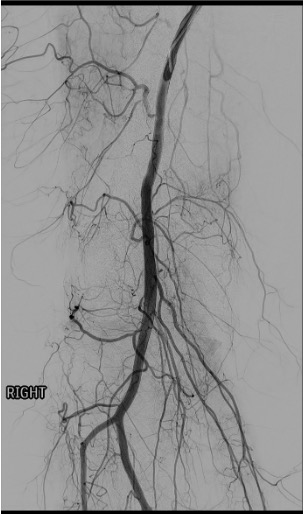

Normal vs. Pathologic Arteriogram

- Normal: Thin, well-defined genicular branches; minimal parenchymal blush in periarticular soft tissues

- OA/synovitis: Markedly increased neovessels; dense, persistent, diffuse synovial blush (hyperemia) — especially in medial and anterior compartments

- Post-arthroplasty hemarthrosis: Focal hypertrophic synovial neovessels, often superomedial distribution

- Compare affected knee arteriogram to published normal anatomy (Fig. 36.4 in source text) — the contrast is striking in symptomatic patients

Popliteal arteriogram — map genicular anatomy

Vessel Identification on DSA

- Popliteal artery: Centerline vessel in the posterior knee; all geniculars arise from it within ~5 cm above and below joint line

- SMGA / SLGA: Arise 3–5 cm above joint line; curve medially or laterally around respective femoral condyles; visible on AP and oblique views

- IMGA / ILGA: Arise at or just below the joint line; smaller caliber; often multiple branches; best seen on oblique views (30–45°)

- Middle genicular: Short posterior branch; may not be selectively catheterized; contributes less to anterior synovial hyperemia

- Use oblique views (30–45° ipsilateral and contralateral) to separate overlapping vessel takeoffs and open the orifices of individual genicular arteries